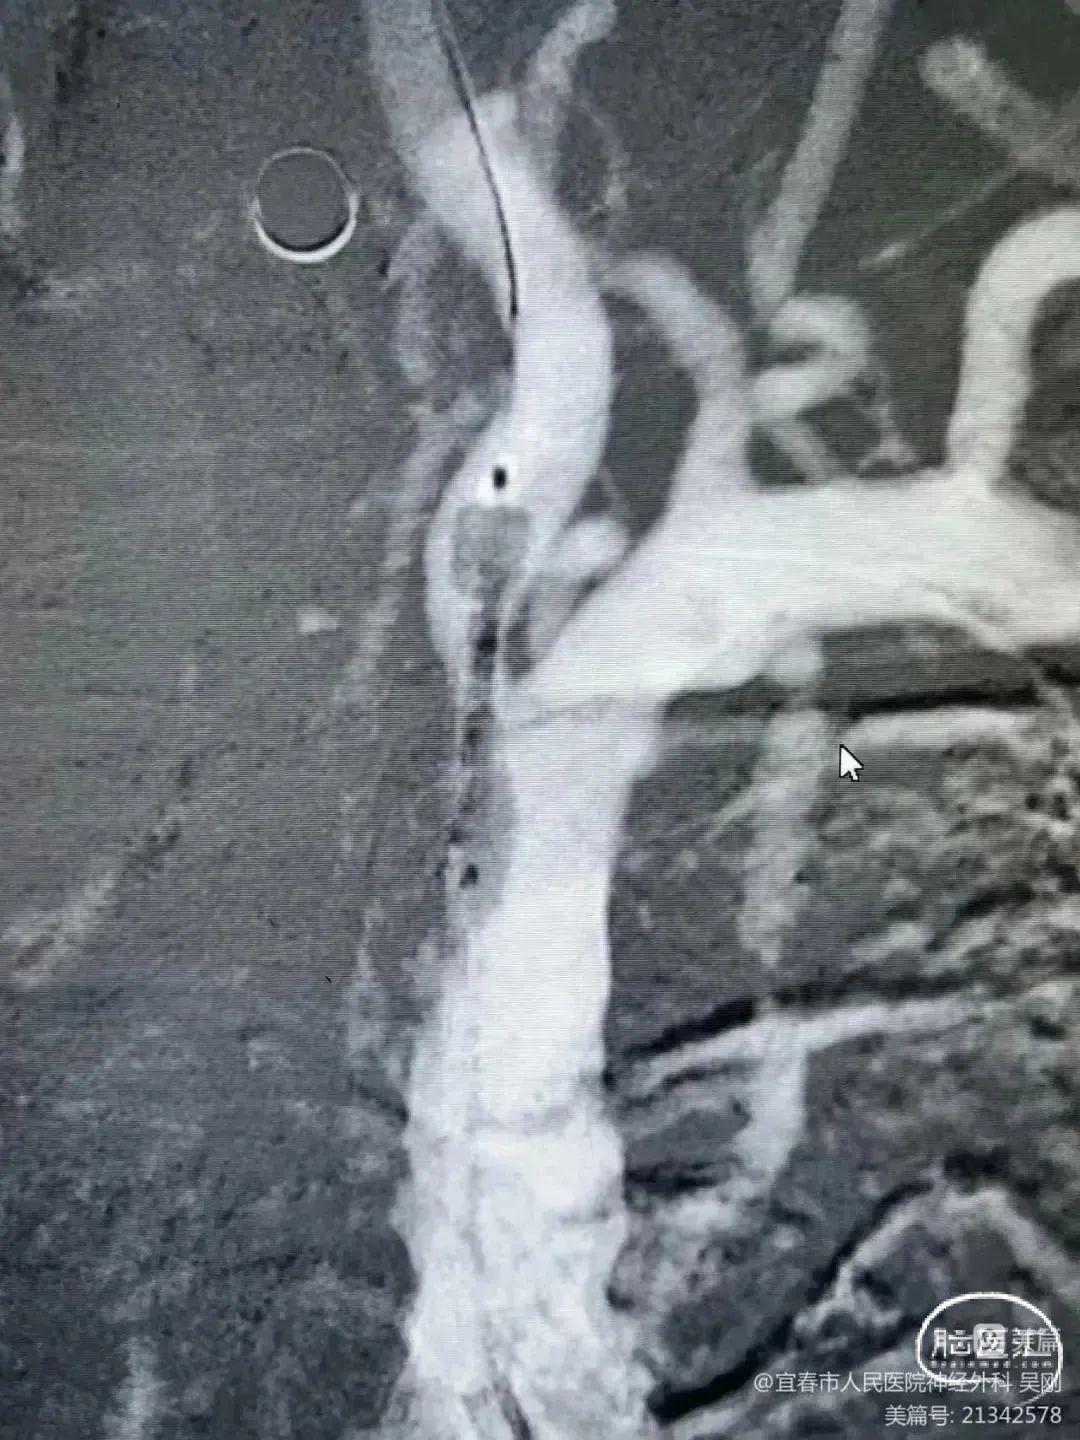

保留微导丝、Guiding回撤到锁骨下,观察椎动脉开口:椎动脉开口无法维持。拟行椎动脉开口支架成形术,选用4mm*15mm Bridge椎动脉雷帕霉素靶向洗脱支架。

操作要点:

释放后注意严格控制血压,球囊不急于撤出,可逐步泄压。

术后造影:

血管再通,前向血流3级。左侧为胚胎型大脑后。

术后用药:替罗非班24小时复查CT后桥接双抗。